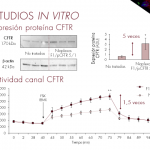

28 Sep September 27th 2022 – Nanoligent SL, a Spanish biotech company specialized in the development of cancer treatments based on unique protein conjugates, today announces the completion of a Seed financing round of total € 2.8 M. The final closing of the Seed round consists of € 1 M investment by i&i Biotech Fund I (i&i Bio), an early-stage Life Science fund with teams in Luxemburg and Prague which is backed by the European Investment Fund. i&i Bio joined previous Nanoligent investors, Italian Angels for Growth, the largest network of business angels in Italy, and AVANTECA Partners, a Swiss privately held[...] 16 Aug The Academic Ranking of World Universities (ARWU), known as Shanghai Ranking, which was made public on August 15, places the Autonomous University of Barcelona among the elite of the 300 best universities in the world. This indicator organizes up to 20,000 university centers worldwide,based on transparent methodology and objective third-party data. ARWU is regarded as one of the three most influential and widely observed university rankings Two of NANBIOSIS Units created by UAB and CIBER-BBN are part of this university: U1 Protein Production Platform (PPP), led by Toni Villaverde, Neus Ferrer and Mercedes Marquez, offer an “tailored” service for the design,[...] 25 Jun The use of protein nanoparticles as biomaterials have been rising in recent years due to their characteristics: high biocompatibility, structural versatility, biodegradability and plasticity of design. We can later incorporate peptide ligands for specific targeting as fusion proteins and use these nanoparticles for targeted nanomedicine. However, not all proteins can be used as scaffolds for targeted drug delivery, as they need to meet certain criteria. First, it is crucial that the proteins used as a scaffold allow site-specific drug conjugation. The stability and proteolysis resistance of these proteins is also important to remain assembled during the bloodstream circulation. In addition,[...] 02 May During the last 27-29 April, the 3rd International Conference on Nanomaterials Applied to Life Sciences 2022 (NALS 2022) has taken place in the Excellence Campus of Universidad de Cantabria in Santander (Spain), organized by the University of Cantabria and Institute Valdecilla-IDIVAL. NALS 2022 has been a multidisciplinary conference series sharing new results and ideas in the fields of biosensors, lab on a chip, drug delivery nanopharmacy. nanobiotechnology, intelligent nanomaterials, magnetic materials, nanotoxicity, antimicrobials, novel applications of 3d bioprinting and nanoimaging. NANBIOSIS has been represented at this edition by members of several of its units, among them we must highlight the set of four ora[...] 28 Feb WHY DO CELEBRATE TODAY THE INTERNATIONAL #RareDiseaseDay? 29 of February is a ‘rare’ date and February, a month with a ‘rare’ number of days, has become a month to raise awareness about rare diseases and their impact on patients’ lives. Since 2008 thousands of events happen every year all around the world and around the last day of February with the aim of improving equity and reducing stigmatization for people who live with more than 6,000 rare diseases. WHAT ARE RARE DISEASES Rare diseases are pathologies or disorders that affect a small part of the population (less than 5 per 10,000 inhabitants) and[...] 03 Feb Barcelona, Spain – Milan, Italy, February 3rd, 2022 – Nanoligent SL, a biotech company specialized in the development of nanotechnology-based cancer treatments, today announces the completion of the first closing of a Seed financing round of €1M. The round has been led by members of Italian Angels for Growth, the largest network of business angels in Italy, through the investment vehicle Nanolinvest, and AVANTECA Partners, a Swiss privately held asset management firm, both specialized in supporting innovative early-stage life-science companies primarily in Europe. An equity campaign, is still ongoing on Doorway, an online investment platform, thus promising to provide additional funding[...] 11 Jan Researchers of NANBIOSIS Units 1 and 18, from CIBER-BBN at the Institut de Biotecnologia i de Biomedicina (IBB-UAB) and the Institut de Recerca Sant Pau (IIB-Sant Pau) presents the finding of a significant antimicrobial activity in the targeting peptide T22, which is used for antitumor therapy directed against CXCR4 + stem cells, with clinical interest in more than 20 types of human cancer, including colorectal cancer. The study describes how said activity has a significant effect on several bacterial species of clinical importance: “we have detected antimicrobial activity associated with T22 and inhibition of biofilm formation on Escherichia coli, Staphylococcus[...] 18 Apr The Project ADVERT (Advanced Extracellular Vesicles for Enzyme Replacement Therapy) is a research valorisation project recently granted by CIBER. The project pursues to advance the development of extracellular vesicles as treatments for lysosomal diseases, specially to bring new therapies to treat FABRY disease. The ADVERT Project will count on the active particpation of two NANBIOSIS units of CIBER-BBN: Unit 20 of the ICTS NANBIOSIS at Vall d’Ebrón Hospital, led by Ibane Abasolo, who coordinates the project. Unit 1 Protein Production Platform (PPP), at the IBB-UAB, led by Neus Ferrer, throught the coordination in the project of José Luis Corchero. T[...]